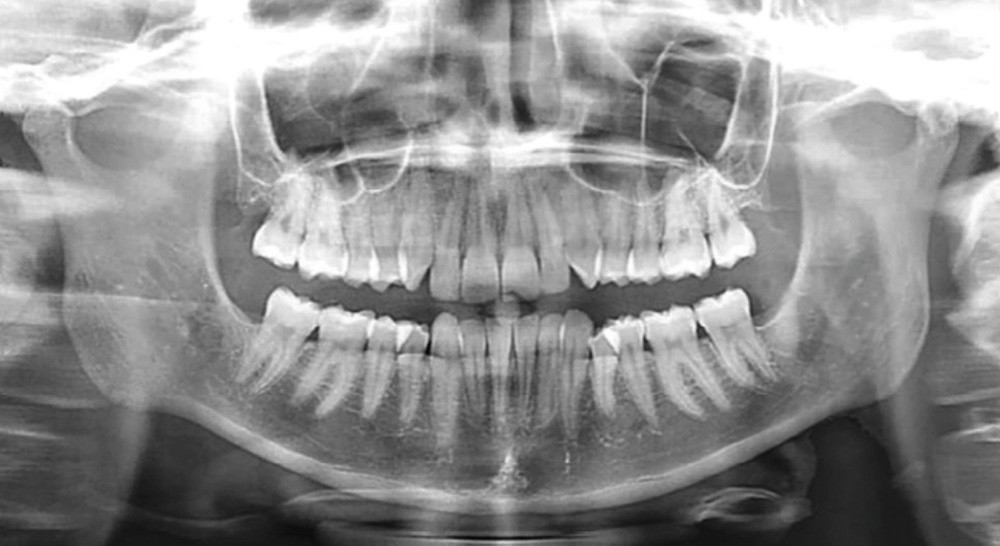

La radiographie panoramique et la téléradiographie de profil objectivent (fig. 3 et 4) :

- un espace rétro-molaire suffisant pour une distalisation ;

- des axes radiculaires molaires favorables à un redressement ;